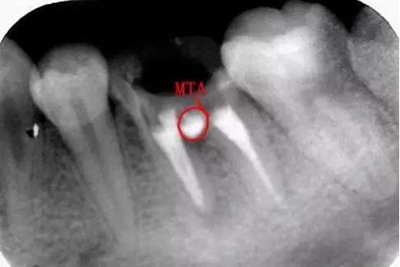

沖洗后封閉氫氧化鈣一周后MTA修補:

MTA:有點太貴啦,這個病號是個在校的大學(xué)生統(tǒng)統(tǒng)的費用700,專門為他訂購的材料,我真的盡力啦。

修補后:

沒有顯微鏡和MTA輸送器做的有點不精致,幸好還有個放大鏡要不更累啦。

期待復(fù)查的效果。。。。